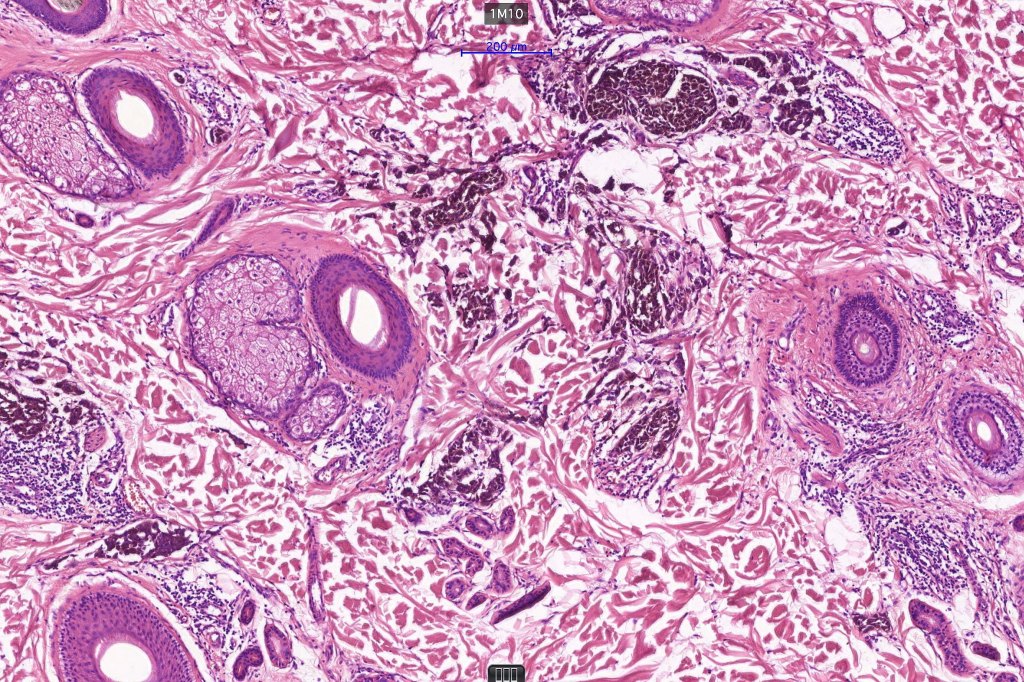

1.typical melanoma in the superficial aspect overlying a deep penetrating nevus-like deeper component

2. typical epithelioid melanoma in the superficial aspect associated with very marked perivascular and appendageal spread giving rise to a plexiform appearance

3. a deep penetrating nevus like lesion showing obvious signs of malignancy including greater pleomorphism than is usually seen combined with excessive mitotic activity, deep mitoses and atypical forms

4. melanoma which shows a deep penetrating architecture although the cytology remains epithelioid throughout